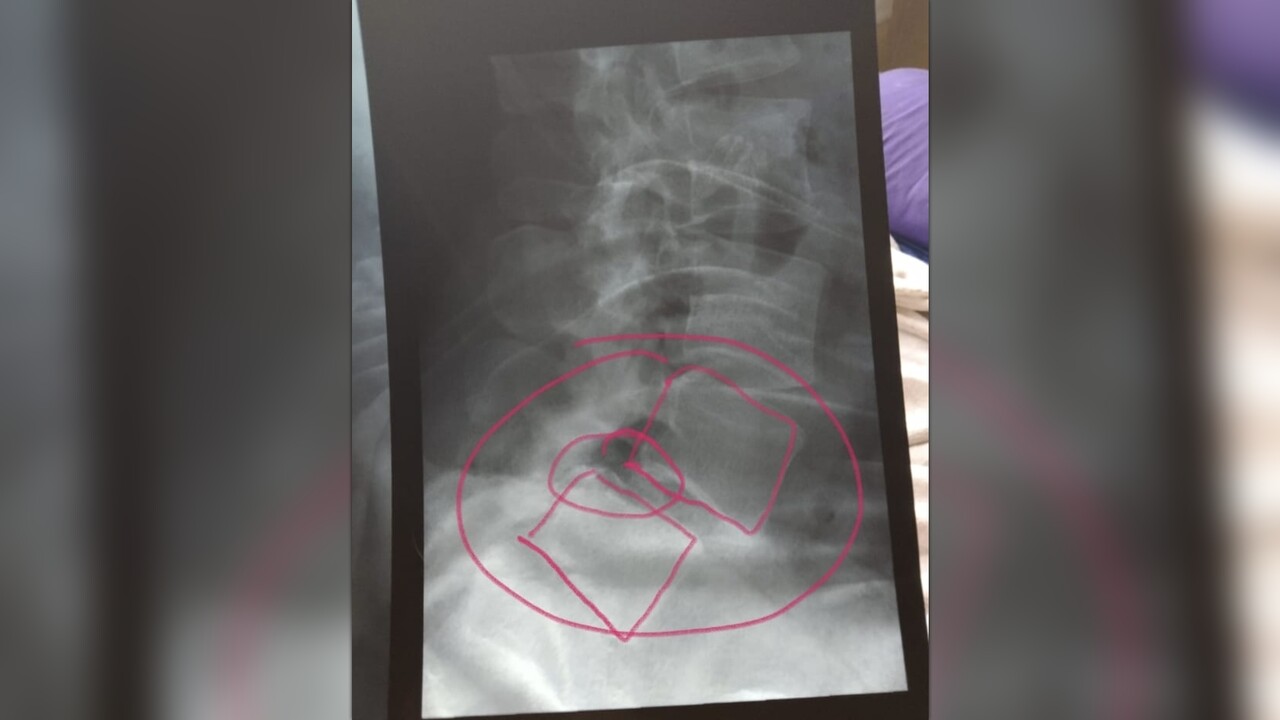

Primero darle las gracias a quien pueda darme una mano, mi situación es muy delicada, soy viuda con 2 hijos, en el año 2018 tuve una caída muy fuerte por la que se me paralizó la pierna derecha por la compresión del nervio ciático, sufrí mucho dolor y 4 meses sin poder caminar, con 4 terapias diferentes y 7 medicamentos logré librarla, siempre quede con molestia, para el 2024 me comenzó en la pierna izquierda con dolores inexplicables, he pasado por estudios y procesos en el Seguro Social, pero no he tenido respuesta de neurocirugia, q es mi

unica solución para regresar una vértebra que está desplazada, ya no

es soportable este dolor por lo q consulte y la cirugía ronda los

14.000$ a 15,000$ USD dinero con el cual no cuento, esa cirugía es de

First of all, thank whoever can give me a hand, my situation is very delicate, I am a widow with 2 children, in 2018 I had a very strong fall by which my right leg was paralyzed due to the compression of the sciatic nerve, I suffered a lot of pain and 4 months without being able to walk, with 4 different therapies and 7 medications I managed to get rid of it, I was always discomfort, by 2024 it started in my left leg with inexplicable pains, I have gone through studies and processes in Social Security, but I have not had a response from neurosurgery, which is my

Only solution to return a vertebra that is displaced, this pain is no longer bearable for what I consult and the surgery is around $14,000 to $15,000 USD money that I do not have, that surgery is of maximum urgency, that is why I come here to request your financial help to be able to do it soon, I thank you in advance.